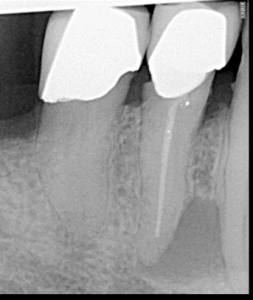

Clinical Cases